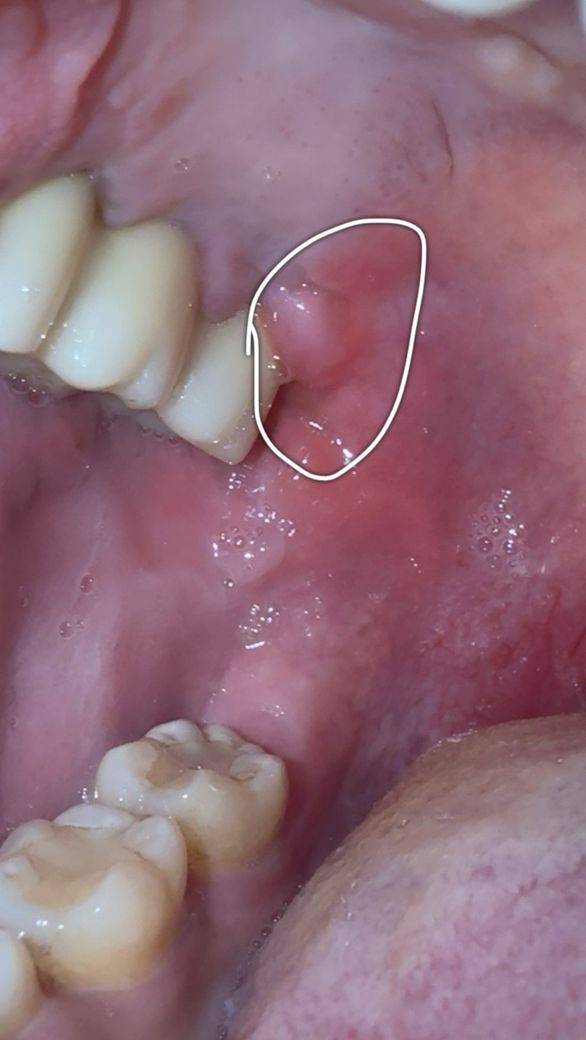

첫번째 사진은 12/16 아침에 일어나서 찍은 사진이며

오늘 아침 뭔가 불편감에 찍어본 사진인데 저렇게 부풀어있고 평소와는 다르기에 면봉으로 살짝 촉진해보니 물컹하더라구요..

• 1번 째 사진